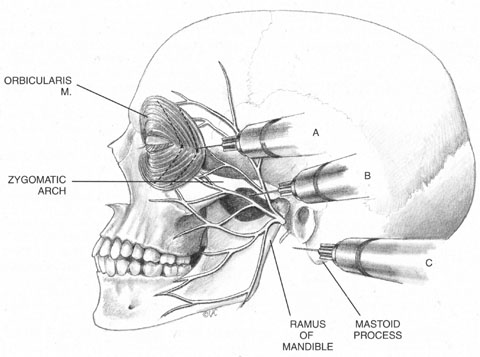

The trigeminal nerve carries the sensory innervation of the eye and adnexa in three divisions: ophthalmic, maxillary, and mandibular. Except for a portion of the sensory input from the lower lid that is carried by the maxillary division, the sensory fibers of the eye and adnexa are found in the ophthalmic division. This division in turn has three components: frontal, lacrimal, and nasociliary, as shown in Figure 1. The frontal nerve usually branches into two more divisions: the supraorbital, which carries sensation from the conjunctiva and skin of the central two-thirds of the upperlid; and the supratrochlear, which carries sensory fibers from the medial third of the upper lid. The lacrimal nerve carries sensory input from the skin and conjunctiva of the lateral aspect of the upper lid.47 The nasociliary nerve carries sensory fibers from the cornea, iris, ciliary body, perilimbal bulbar conjunctiva, and optic nerve sheath; these fibers proceed through its long ciliary branches and sensory root to the ciliary ganglion. The infratrochlear branch of the nasociliary nerve carries sensory input from the medial canthus, medial portion of lower lid skin and conjunctiva, caruncle, lacrimal sac, and canaliculi.

Once it is known which branches are responsible for carrying sensory input from which structures, an approach can be planned that has a reasonable chance of blocking the targeted area. Because, for example, the nasociliary nerve carries fibers that pass through the intraconal space, a standard intraconal retrobulbar block may provide excellent intraocular and partial surface anesthesia. It could not be expected, however, to effectively block the conjunctiva of the upper or lower lids or the lateral aspect of the globe. Because the frontal and lacrimal branches enter the orbit through the superior fissure, above the annulus of Zinn, and the maxillary division enters the orbit through the infraorbital foramen, below the annulus, an intraconal approach probably would not effectively block the structures these branches innervate. If an intraconal retrobulbar block is the only one administered before surgery, patients can be expected to feel irrigating solutions being dropped on the conjunctiva, away from the limbus; they also will be aware of the lid speculum and any manipulation of the lateral surface of the globe. They will probably attempt to close the eye in response to these stimuli. This is the basis for the traditional facial–retrobulbar block combination.

As has been mentioned, numerous facial blocks have been devised to prevent patients from squeezing the eye shut during surgery. None of these blocks keeps patients from wanting to close the eye—only from succeeding. Because the facial block also involves added discomfort, many anesthesiologists and surgeons provide intravenous sedation along with it. Thus, limiting the initial block to the intraconal retrobulbar space also limits its potential benefits, requiring two supplemental procedures. Anatomy determines effect.